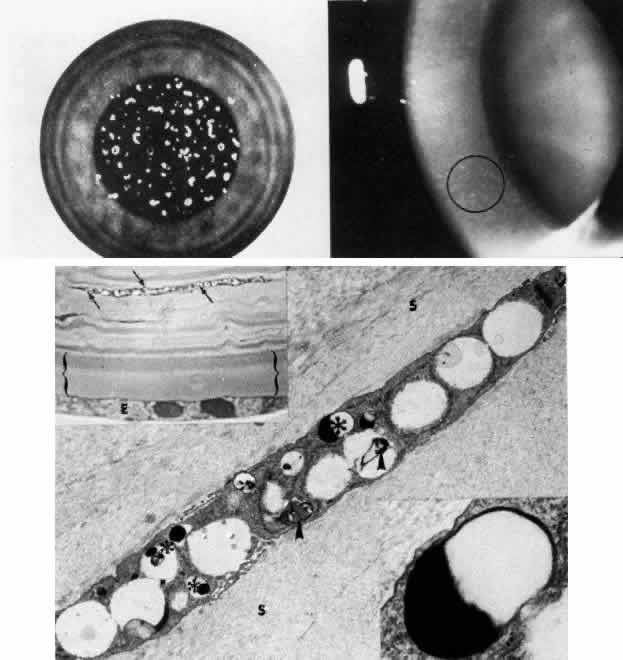

Fig. 4. Sclerocornea. Schematic drawing of ocular features Top left. In a minimally affected patient with additional findings of ptosis, strabismus, and hearing loss, only the peripheral cornea is opacified. Top center. In this advanced case with chromosomal translocation and multiple congenital abnormalities, the entire cornea is sclerified and the fine vascular arcades extend centrally from the conjunctiva and sclera. Top right. Light micrograph of anterior cornea shows edematous disorganization of epithelium, fragmentation of Bowman's membrane (B), and interstitial vascularization (V) (hematoxylin-eosin, × 200). Middle left. Transmission electron micrograph of normal human corneal stroma is shown for comparative purposes. Note uniform 240- to 260-nm collagen fibril diameter (× 50,000). Middle right. Transmission electron micrograph of sclerocornea at same magnification shows disorganized array of collagen fibrils that measure as much as three times normal diameter (× 50,000). Bottom. Transmission electron micrograph of posterior cornea shows abnormal Descemet's membrane of less than 1μm thickness (DM, bracketed) and attenuated endothelial cells (× 10,500). (Schematic. Grayson M: Diseases of the Cornea, p 32. St. Louis, CV Mosby, 1979; Top center and right. Rodrigues MM, Calhoun J, Weinreb S: Sclerocornea with an unbalanced translocation [17p, 10q]. Am J Ophthalmol 78:49, 1974)

Ultrastructural studies22,46,47 have shown the involved stroma to assume the morphologic features of scleral tissue, with irregularly arranged collagen fibrils of variable and immensely enlarged diameter for corneal tissue (up to 150 nm, comparable to normal scleral collagen). The precise lamellar organization of normal corneal stroma is not present; thus optical clarity is not achieved. Various abnormalities of endothelium and Descemet's membrane exist, from attenuation to focal absence. Descemet's membrane is generally thin, with multilaminar deposition of basement membrane-like collagen.